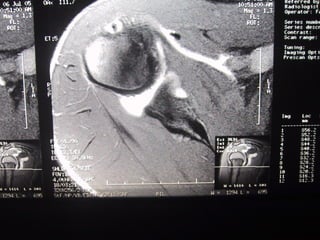

Case 7   Supraspinatus full thickness tear